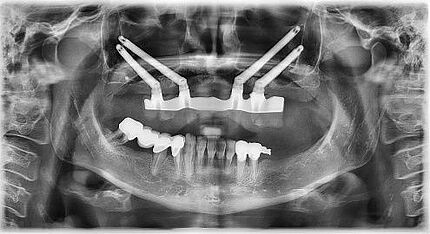

In den letzten Jahren ist eine Zunahme des Interesses an Knochenaugmentationen mit nicht erhaltungs- würdigen Zähnen erkennbar. Das Verwerfen von extrahierten Zähnen ist zurzeit noch tägliche Routine in Zahnarztpraxen und Kliniken. Dieser Fallbericht illustriert die Situation eines 62-jährigen Patienten, bei dem nach Entfernung der Oberkieferfrontzähne der Alveolarfortsatz einen komplexen knöchernen Defekt aufwies. Die Schaltlücke wurde zweizeitig rekonstruiert. Hierbei wurde der knöcherne Defekt mittels der Tooth Shell Technique nach Korsch unter Verwendung von autologem Dentin rekonstruiert und mit zwei Implantaten sowie Implantatkronen prothetisch versorgt. Abschließend erfolgte eine Transplantation von freier keratini-sierter Schleimhaut zur Rekonstruktion des Vestibulums und zur Stabilisierung der periimplantären Mukosa.

Zeitschrift: ZWP-Online – Implantologie Journal

Ausgabe: 05/2023

Autoren: Prof. Dr. Michael Korsch, M.A.,

Dr. Abdel-Karim Mamar